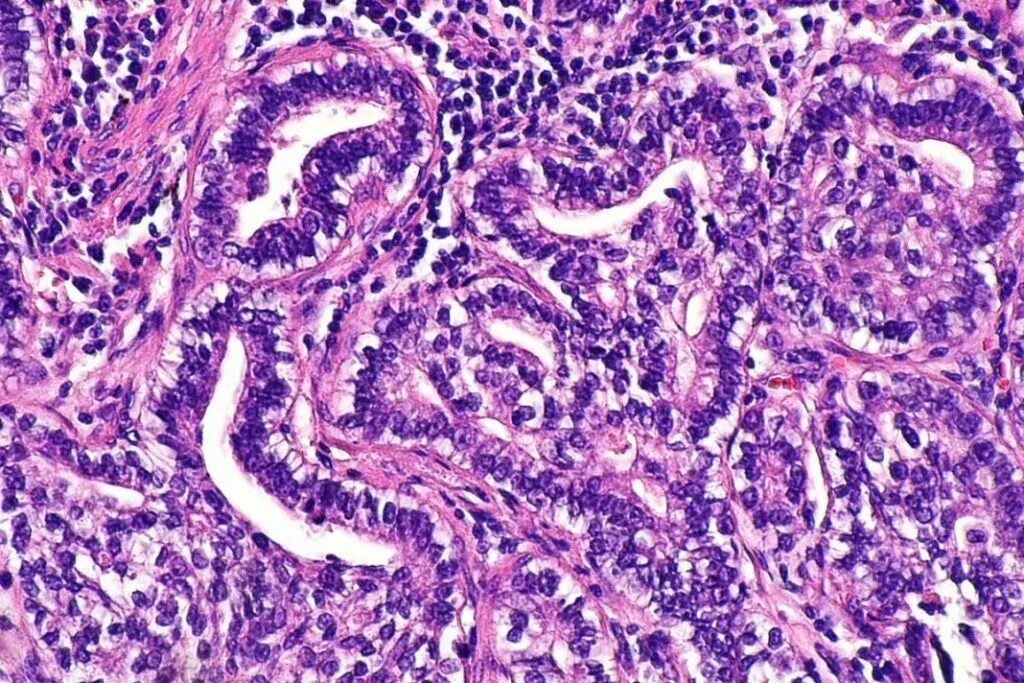

Гистология э